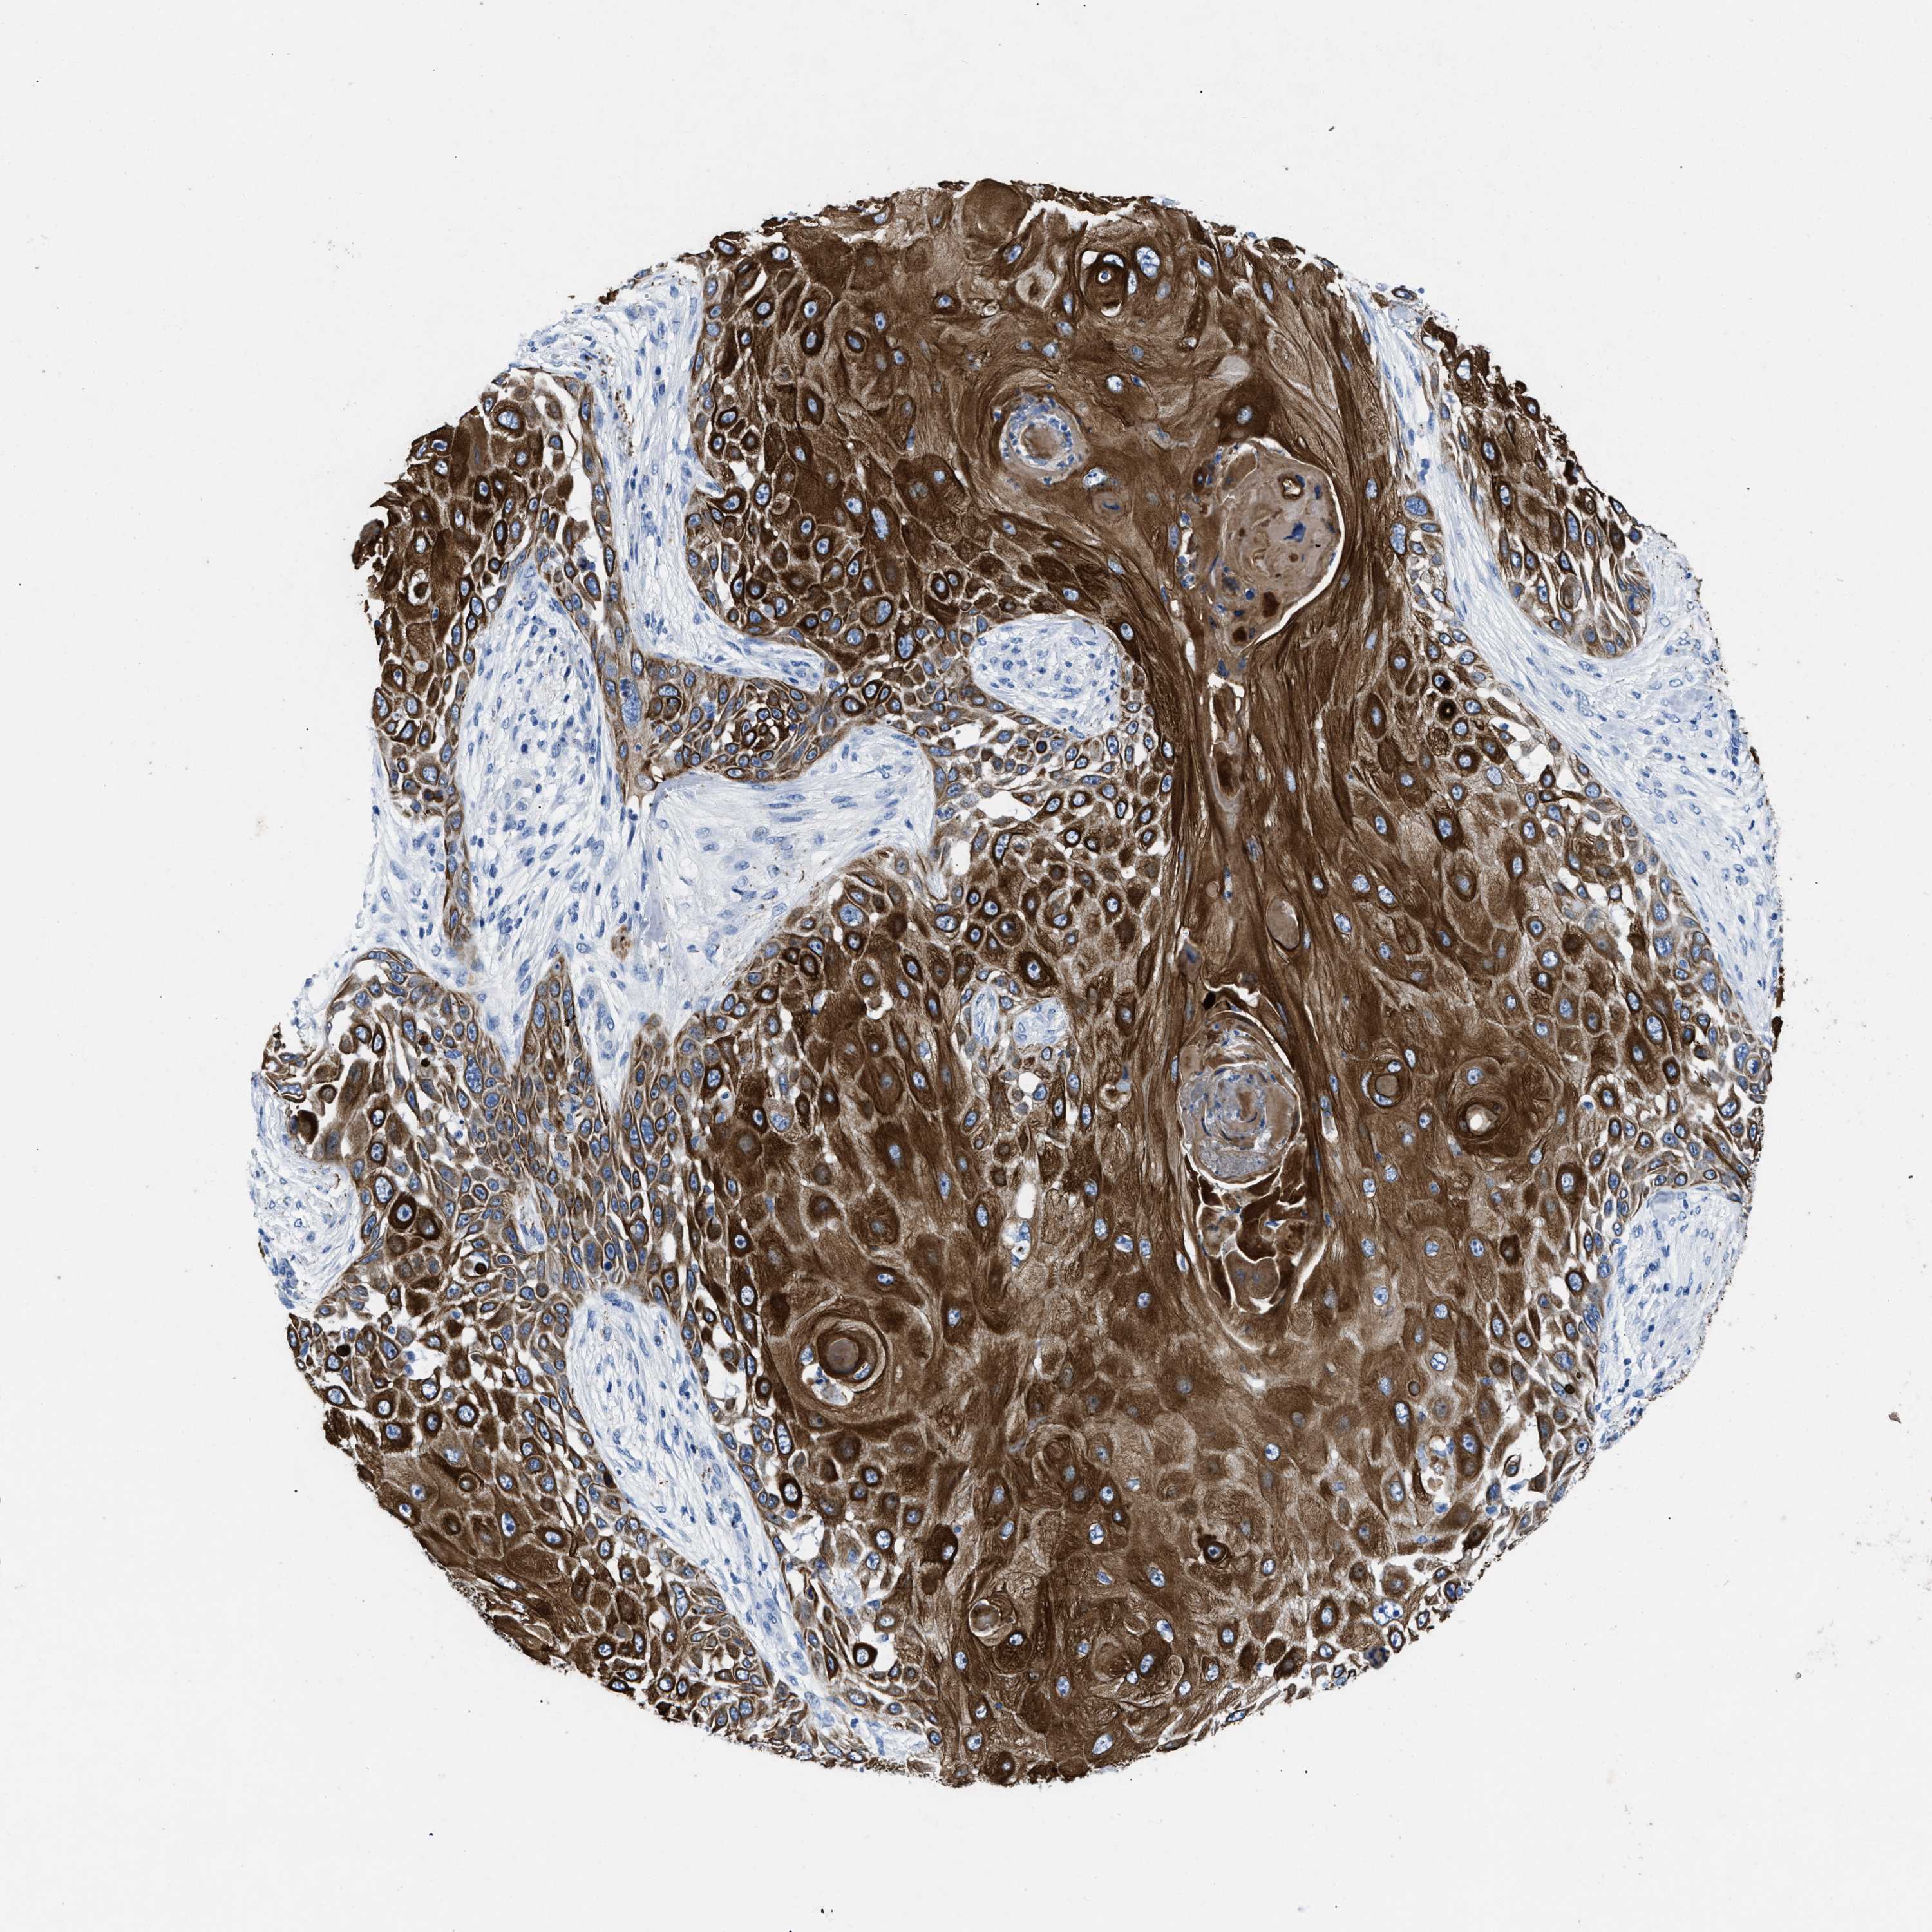

SKIN CANCER - Protein expressioni

A mouse-over function shows sample information and annotation data. Click on an image to view it in a full screen mode. Samples can be filtered based on level of antibody staining by selecting one or several of the following categories: high, medium, low and not detected. The assay and annotation is described here.

Each image is clickable and will lead to virtual microscopy that enables deeper exploration of all samples and also displays staining intensity scores, fraction scores and subcellular localization as well as patient and tissue information for each sample.

Antibody HPA018216

Staining

High

Intensity

Strong

Quantity

>75%

Location

Cytoplasmic/membranous

Squamous cell carcinoma in situ, NOS